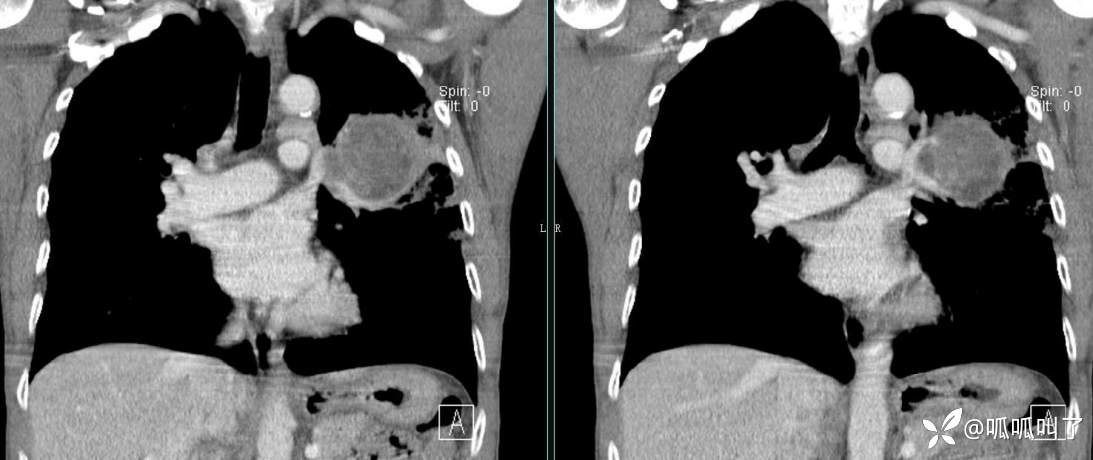

胸部CT平扫和增强: